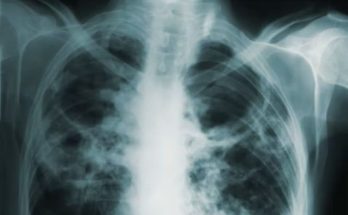

Alarming report! WHO study reveals TB claimed 1.2 million lives in 2024

IBNS-CMEDIA: Tuberculosis (TB) remains one of the world’s deadliest infectious killers, claiming over 1.2 million lives and affecting an estimated 10.7 million people last year, according to the WHO Global Tuberculosis …